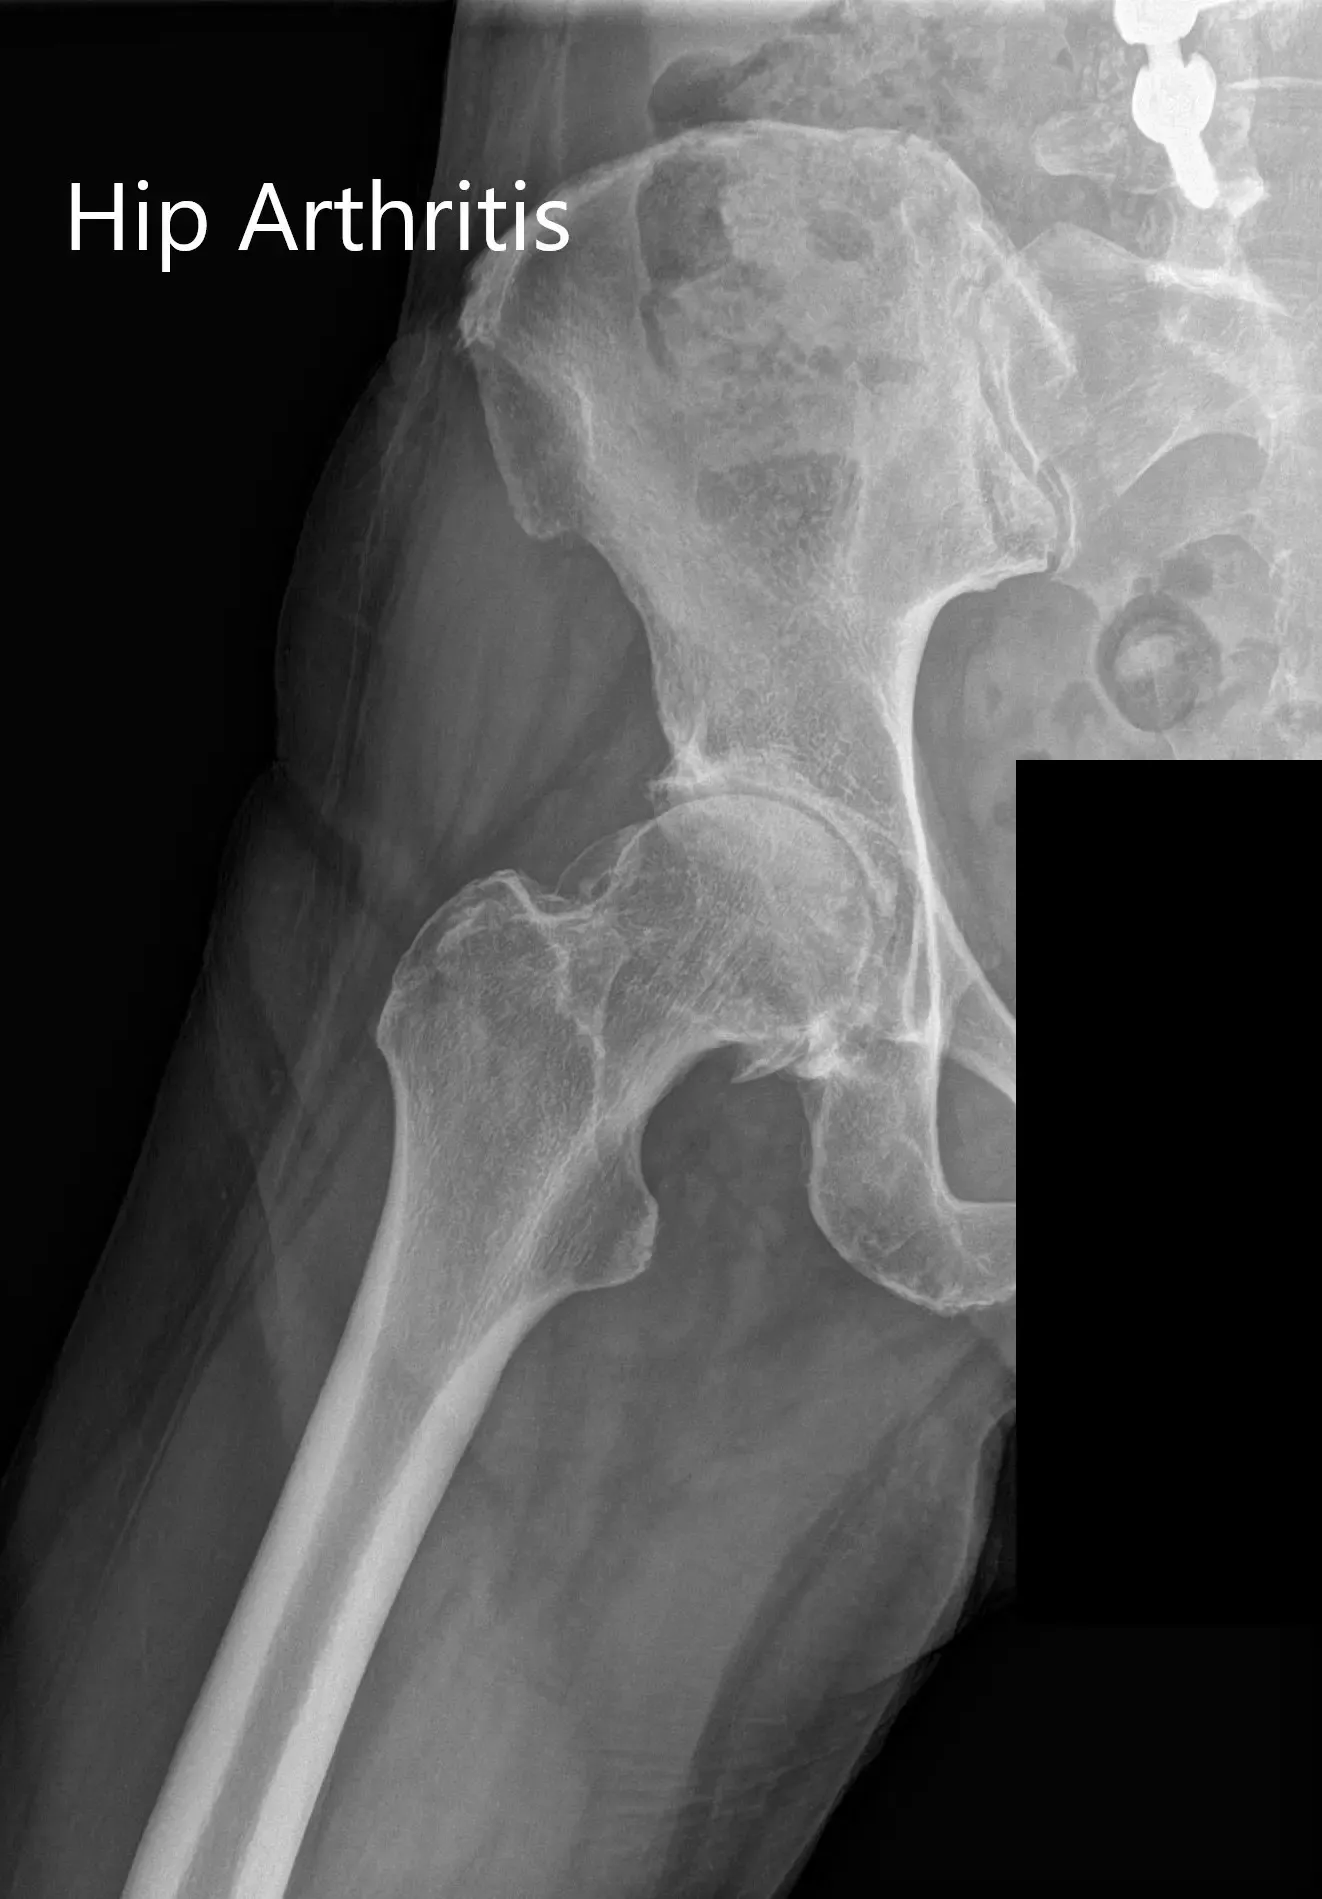

Imaging revealed osteoarthritis of the right hip with joint space reduction and osteophytes. The patient was advised right total hip robotic replacement. The risks, benefits, and alternatives were discussed with the patient at length and she agreed with the plan.

Preoperative X-ray Showing the AP and lateral views of the right hip.